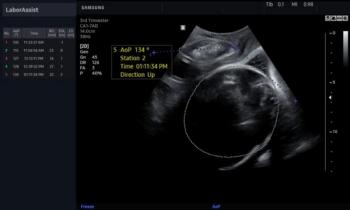

Ultrasound system provides obstetric measurements during labor in seconds, eliminating the need for digital vaginal exams and helping to side-step C-sections.